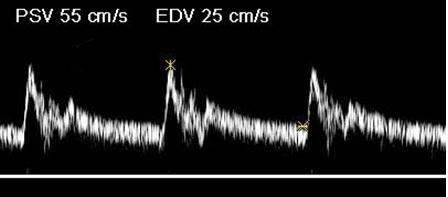

Where is the waveform?

ICA